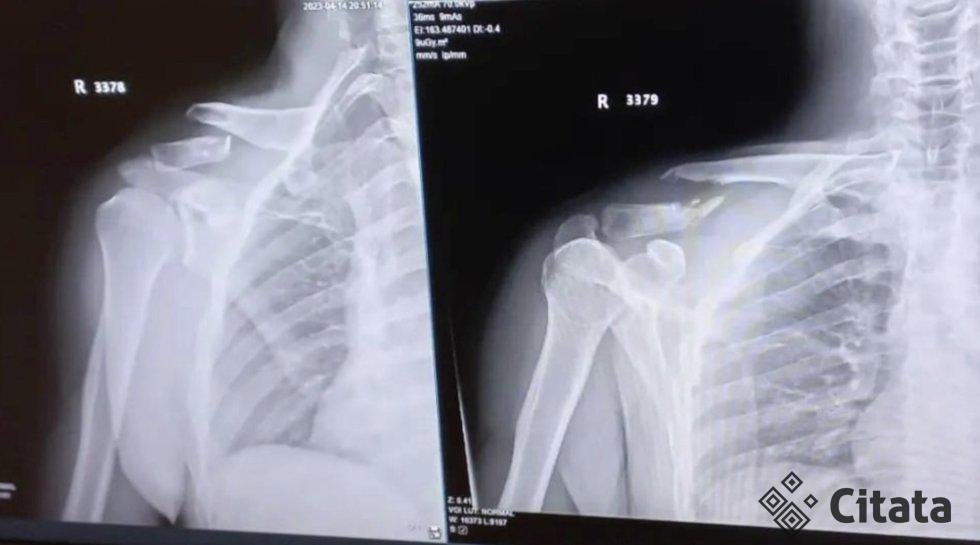

„Padarė rentgeno nuotrauka, suleido nuskausminamuosius ir išleido namo. Sakė, kad savaitės eigoje, jeigu viskas gerai, atsiras vietų, nes jų nėra ir padarys operaciją. Aš pats nustebau, tokį lūžį pamatęs išsigandau“, – pasakojo vyras.

„Pas mane jau ten susikryžiavę su atplaišom… Gavau plokštę su septyniais varžtais. Sunkus lūžis šiaip. Nusiunčiau nuotrauką ir sako okay, atvažiuok rytoj, iškart darom, nes iš tikrųjų atrodė rimta. Tai labai džiaugiuosi, esu dėkingas“, – pasakojo Tadas.

Tado raktikaulio rentgeno nuotrauką pamatę sveikatos apsaugos ministras Arūnas Dulkys ir Seimo Sveikatos reikalų komiteto pirmininkas Antanas Matulas trauko pečiais. Tokia ta mūsų sistema, kurioje yra visko – tame tarpe ir klaidų.

„Pagal tai, ką aš mačiau rentgene, turėjo būti kitaip sprendžiama. Šitą lūžį gydo bet kuriame rajone – ir gydo gerai – tai tikrai turėjo būti išspręsta, nepaleistas žmogus“, – sakė A. Matulas.